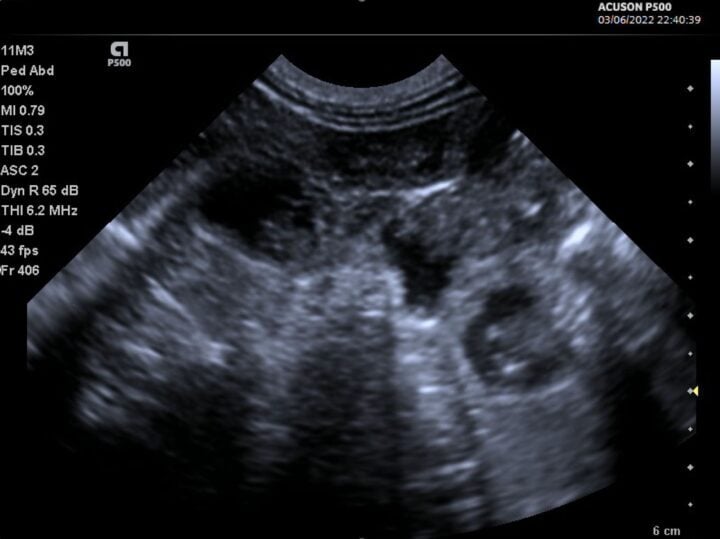

More advanced users may begin to spot foetal abnormalities, such as hydrocephalus, foetal anasarca or bowel obstructions, due to the ease at which ultrasound can image fluid (Figure 4). This is a clear advantage of the veterinarian performing scans in-house over the lay scanner, who would need to refer such findings.

- Use the highest frequencies possible on your transducer: if you have a high-frequency transducer, it is possible to obtain outstanding images on small mammals. Linear probes are ideal for this, but a microconvex probe operating at the top of its frequency range will deliver great images as well (Figure 6)